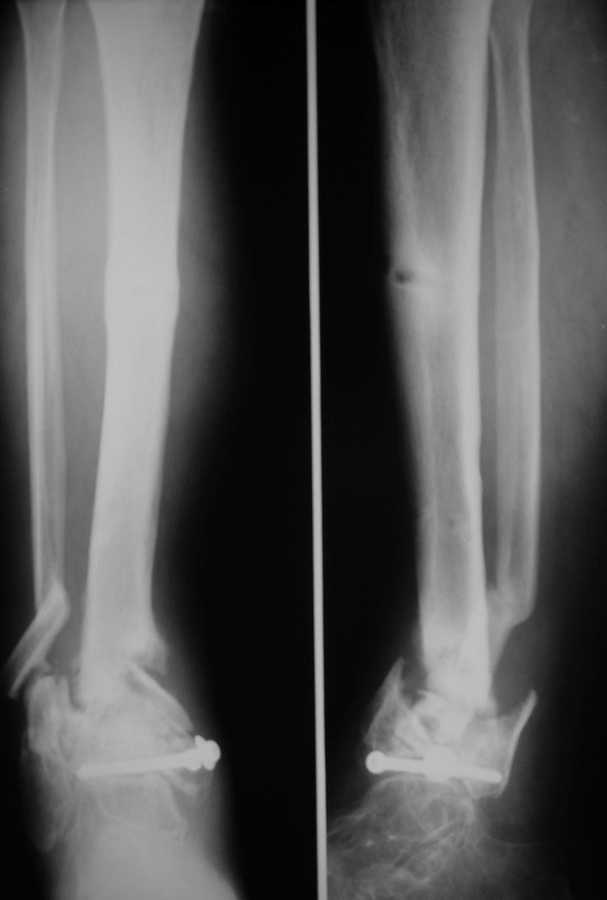

Здравствуйте коллеги! К нам поступил пациент 52 лет. Травму получил два года назад,открытый перелом н/3 костей голени.

Со слов больного год лечили аппаратом, винты ввели при ПХО, потом ещё год ходил в гипсовой повязке.Сейчас ложный сустав в н/3, патологическая подвижность при попытке опоры.Наш вариант лечения: резекционная остеотомия малоберцовой, удалить винты,остеосинтез стержнем с рассверливанием и блокированием через пятку, естесственно с артродезом.Кожа чистая, хотя и в рубцах. Или опять аппарат?